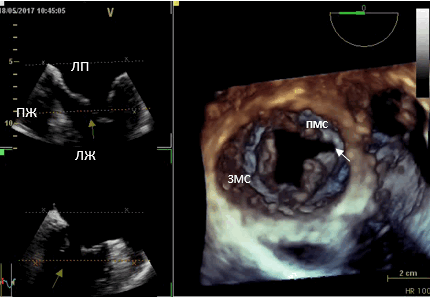

Данные интаоперационной 3D ЧП ЭхоКГ: Митральный клапан: ФК 44 мм, створки уплотнены, расщепление передней створки от свободного края до фиброзного кольца в сегменте А 2, движение створок разнонаправленное. Градиент давления максимальный — 6,2 мм рт.ст., средний 2,1 мм рт.ст. Регургитация выраженная: vena contracta - 0,9 см, площадь потока регургитации — 11,4 см², в непрерывноволновом допплеровском режиме плотный поток регургитации, радиус PISA — 1,0 см. Регургитация — эксцентричная, по боковой стенке ЛП.

Рис. 1. Трёхмерная чреспищеводная эхокардиография. Среднепищеводный доступ. Трёхмерная реконструкция митрального клапана. (ЛП — левое предсердие, ЛЖ — левый желудочек, ПЖ— правый желудочек, ПМС — передняя митральная створка, ЗМС — задняя митральная створка). Расщепление передней митральной створки (белая стрелка).